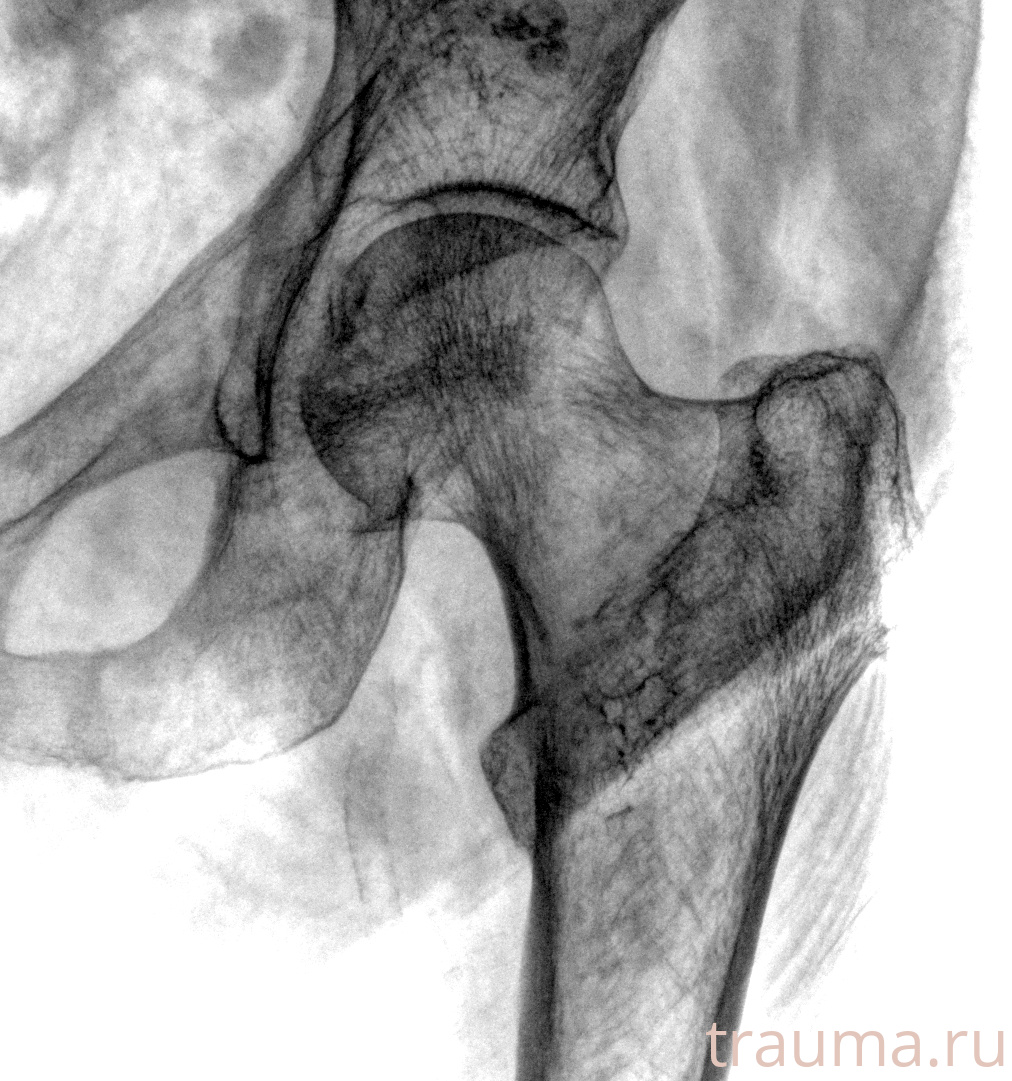

Рентген на дому: по вашему адресу приезжает врач-рентгенолог, травматолог-ортопед с мобильным рентгеновским аппаратом, проводит диагностику травмы или заболевания, делает необходимые рентгенограммы, дает рекомендации по дальнейшему лечению. Получить качественные снимки в домашних условиях возможно благодаря уникальной методике, разработанной МосРентген Центром для института  Склифосовского